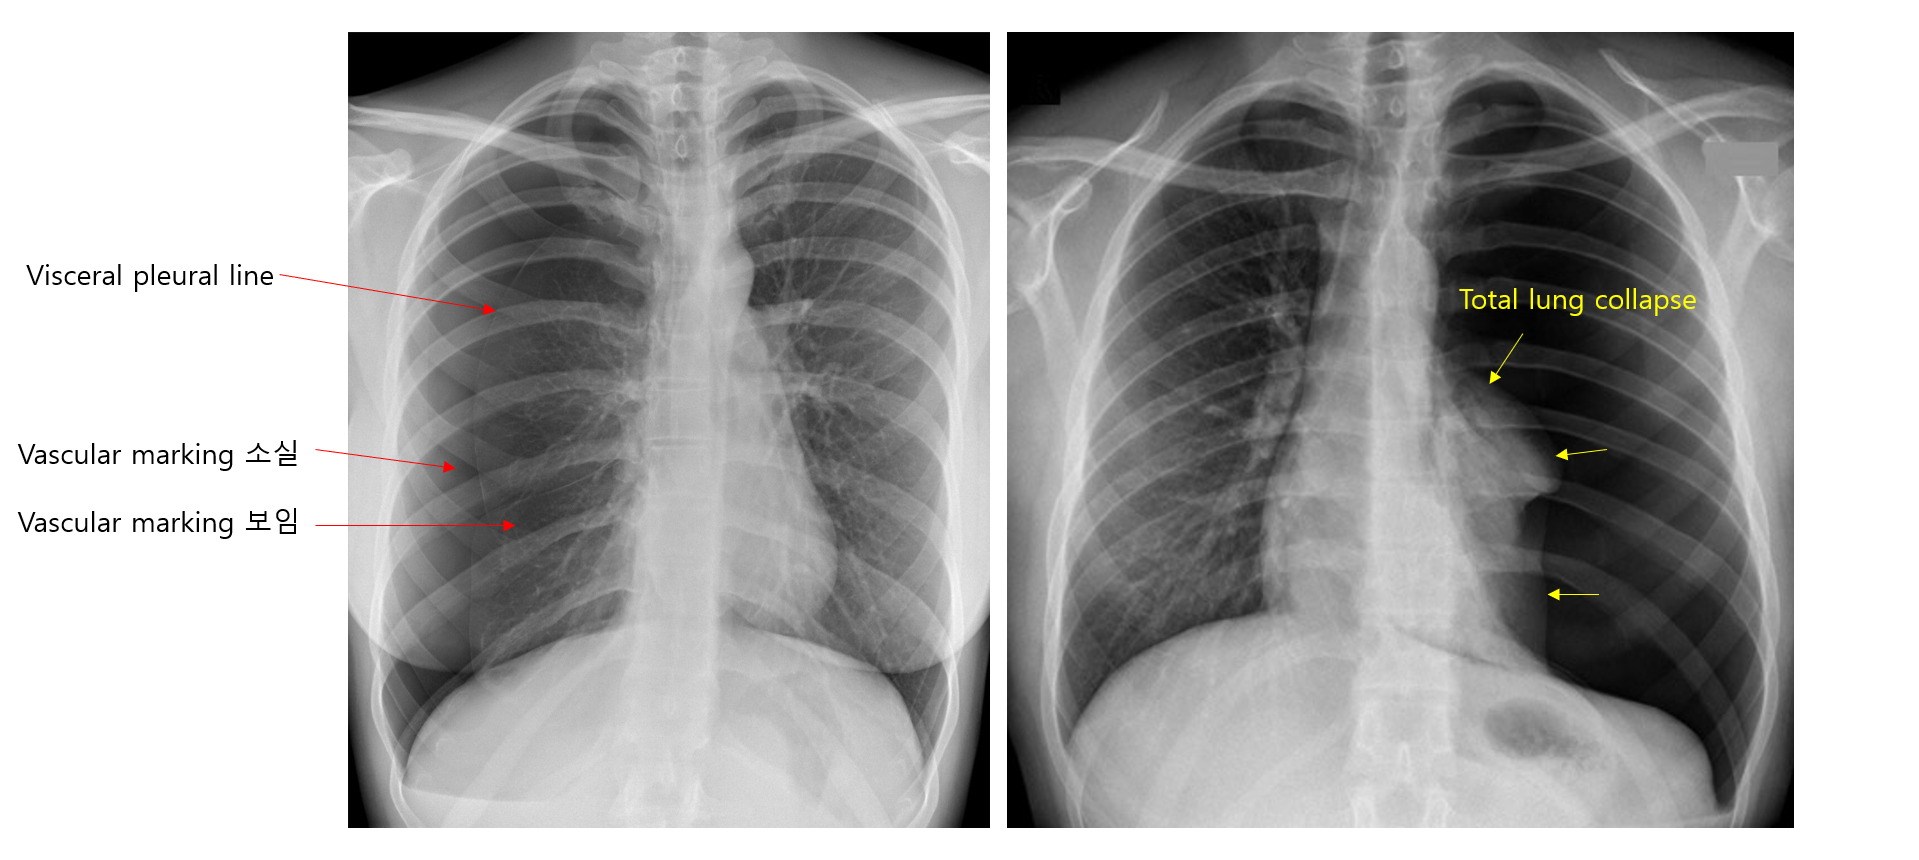

4) 검사소견: CXR

(1) 얇은 pleural line이 보임: Visceral pleura가 보이는 것

기흉의 부피가 커서 폐가 collapse된 경우 line의 형태로 보이지 않을 수 있음

(2) Pleural line 바깥쪽으로 vascular marking의 소실

* 단순히 pleural line이 보이는 것뿐만 아니라, pleural line이 흉강을 따라 끊어지지 않고 tracing이 가능해야 하며 vascular making의 소실이 동반되어야 기흉으로 진단할 수 있다. 피부가 접혀있는 흔적(skin fold), scapula 등이 pleural line으로 오인될 수 있기 때문이다.

② 이로 인해 흉막강 내 공기가 쌓여 흉막강 내압↑ → 한쪽 폐의 total collapse

(1) 종격동이 기흉의 반대편으로 이동

(2) 기흉과 같은 쪽의 횡격막이 아래로 눌림

(3) 기흉과 같은 쪽의 intercostal space가 위아래로 팽창